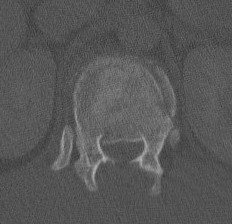

CT

Look for canal compromise

Retropulsed fragments

- always between pedicles

- typically one or two main fragments (saloon door)

- assess canal compromise